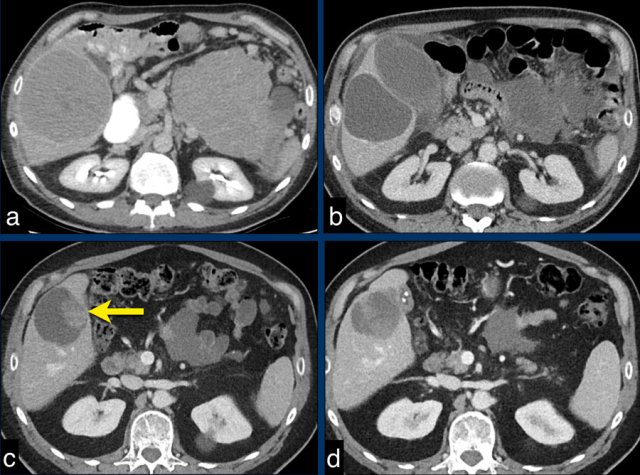

The CT images of a 82-year-old male show liver metastases of a GIST at baseline (arrowheads).

All metastases decrease somewhat in size after treatment with imatinib, but the most remarkable difference is a decrease in density.

This is considered to be a good response according to the Choi criteria.

The CT images in a 66-year-old male show liver metastases of a GIST at diagnosis (a).

At 3 months after treatment with imatinib there is a good response (b).

At a follow up scan at 1 year there is a  recurrence (arrow in c).

At a  follow-up after 2nd line treatment with sunitinib there is still tumor progression, but the size remains the same (d).